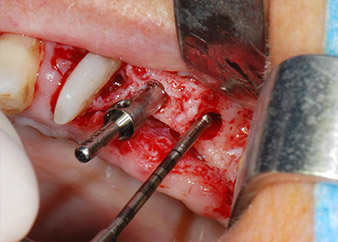

Vor der Insertion der Implantate wurde infiziertes Weichgewebe im Implantationsbereich und um das Abutment mit einem Instrument entfernt, das laut Hersteller primär zur Knochenbearbeitung und zum Sammeln von Knochenspänen vorgesehen ist (Piezomed, Einsatz B5) (Abb. 6 und 7).

Im folgenden Schritt wurde das jeweilige Implantatbett an den Positionen 25 und 26 mit rotierenden Instrumenten in einem Winkelstück mit einem Übersetzungsverhältnis von 20:1 (WS-75 L G, W&H) und einem vor Kurzem aktualisierten leistungsstarken Implantatmotor präpariert (Implantmed, W&H) (Abb. 8 und 19).